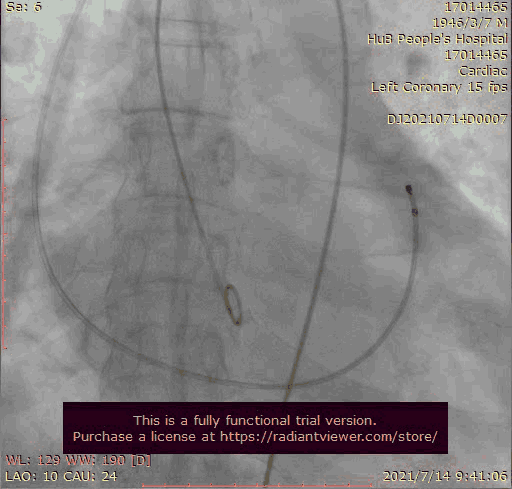

输送器跨瓣

瓣膜稍高位释放

在放射科,超声科和麻醉科的通力协作下,顺利完成了术前准备,术者团队在术中谨慎建立轨道,根据主动脉根部造影的结果选择合适的跨瓣体位。

主动脉根部造影